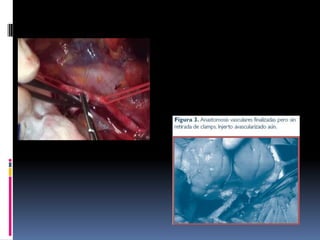

TÉCNICA QUIRÚRGICA

CIRUGÍA DE BANCO:

Consiste en preparar el

riñón para su posterior

implante.

TÉCNICA QUIRÚRGICA PASOS

Posición de decúbito

supino.

Exponemos los vasos

ilíacos y la cúpula

vesical.

IMPLANTE

HETEROTÓPICO

Examinar los vasos:

seleccionar zona de

anastomosis

Colocamos el riñón en

su posición final y

elegimos la longitud de

los vasos

Se disecan ambos

vasos, ligando y

seccionando los

linfáticos perivasculares

El orden de las

anastomosis debe ser

siempre:

venosa, arterial y

urinaria.